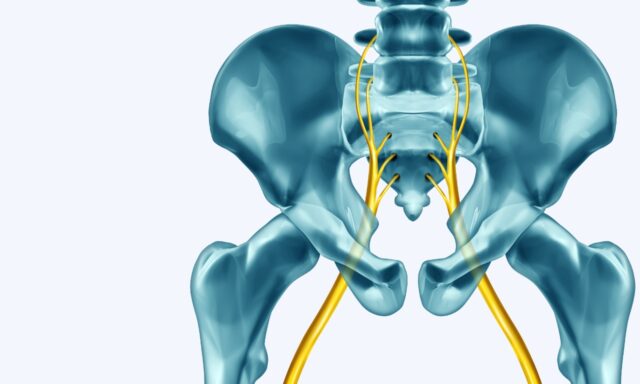

腰椎综合征

说明

在本期节目中,亚当-多布森(Adam Dobson)将与我们一起讨论腰椎综合征的所有问题--从他对病情的定义到排除严重病变的方法,以及他将如何治疗腰椎综合征患者。 他还分享了自己患腰椎综合症的亲身经历。